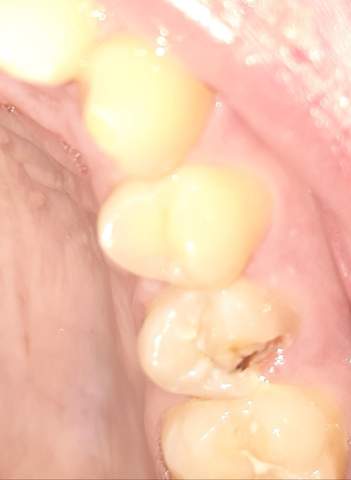

Backenzahn abgebrochen

Bei Backenzähnen kommt es manchmal . Bei einem abgebrochen Zahn ist zu jedem Zeitpunkt ein erhöhtes Karies- sowie Entzündungsrisiko vorhanden.